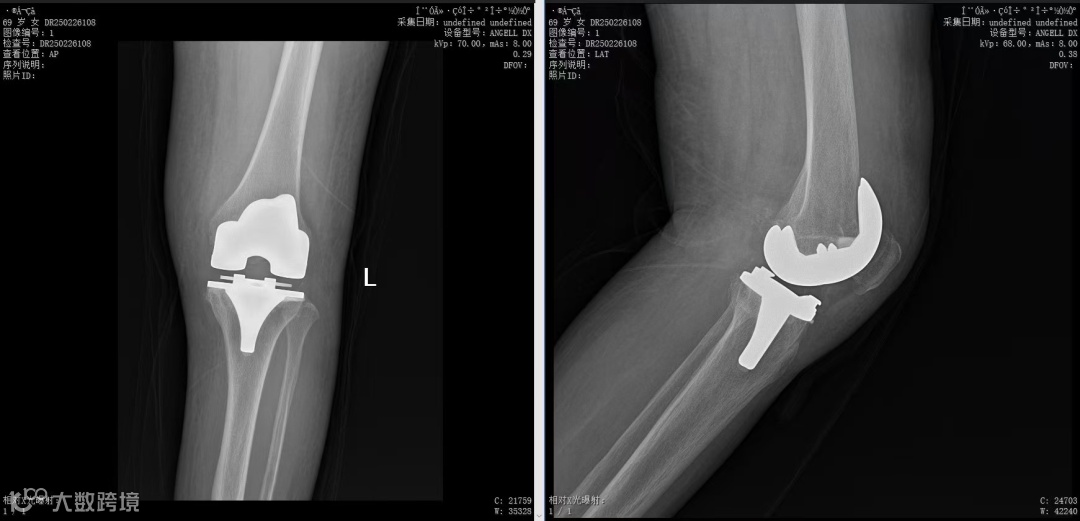

对于这例终末期骨性关节炎,西航医院骨科团队在主任路江鸿的带领下为李阿姨实施了全膝关节表面置换术,手术过程顺利,术后疼痛缓解,第二天便在医护人员指导下开始康复训练,借助助行器已下地行走。复查显示假体位置精准,关节功能接近自然状态。

李阿姨术后影像